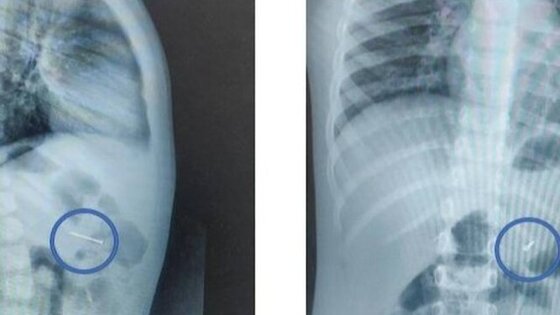

Сначала специалисты сделали рентген, который подтвердил наличие гвоздя в желудке. Затем с помощью эндоскопических щипцов они захватили предмет за острый конец и вытащили через рот. Процедура заняла около 20 минут, отметил Мусаев.